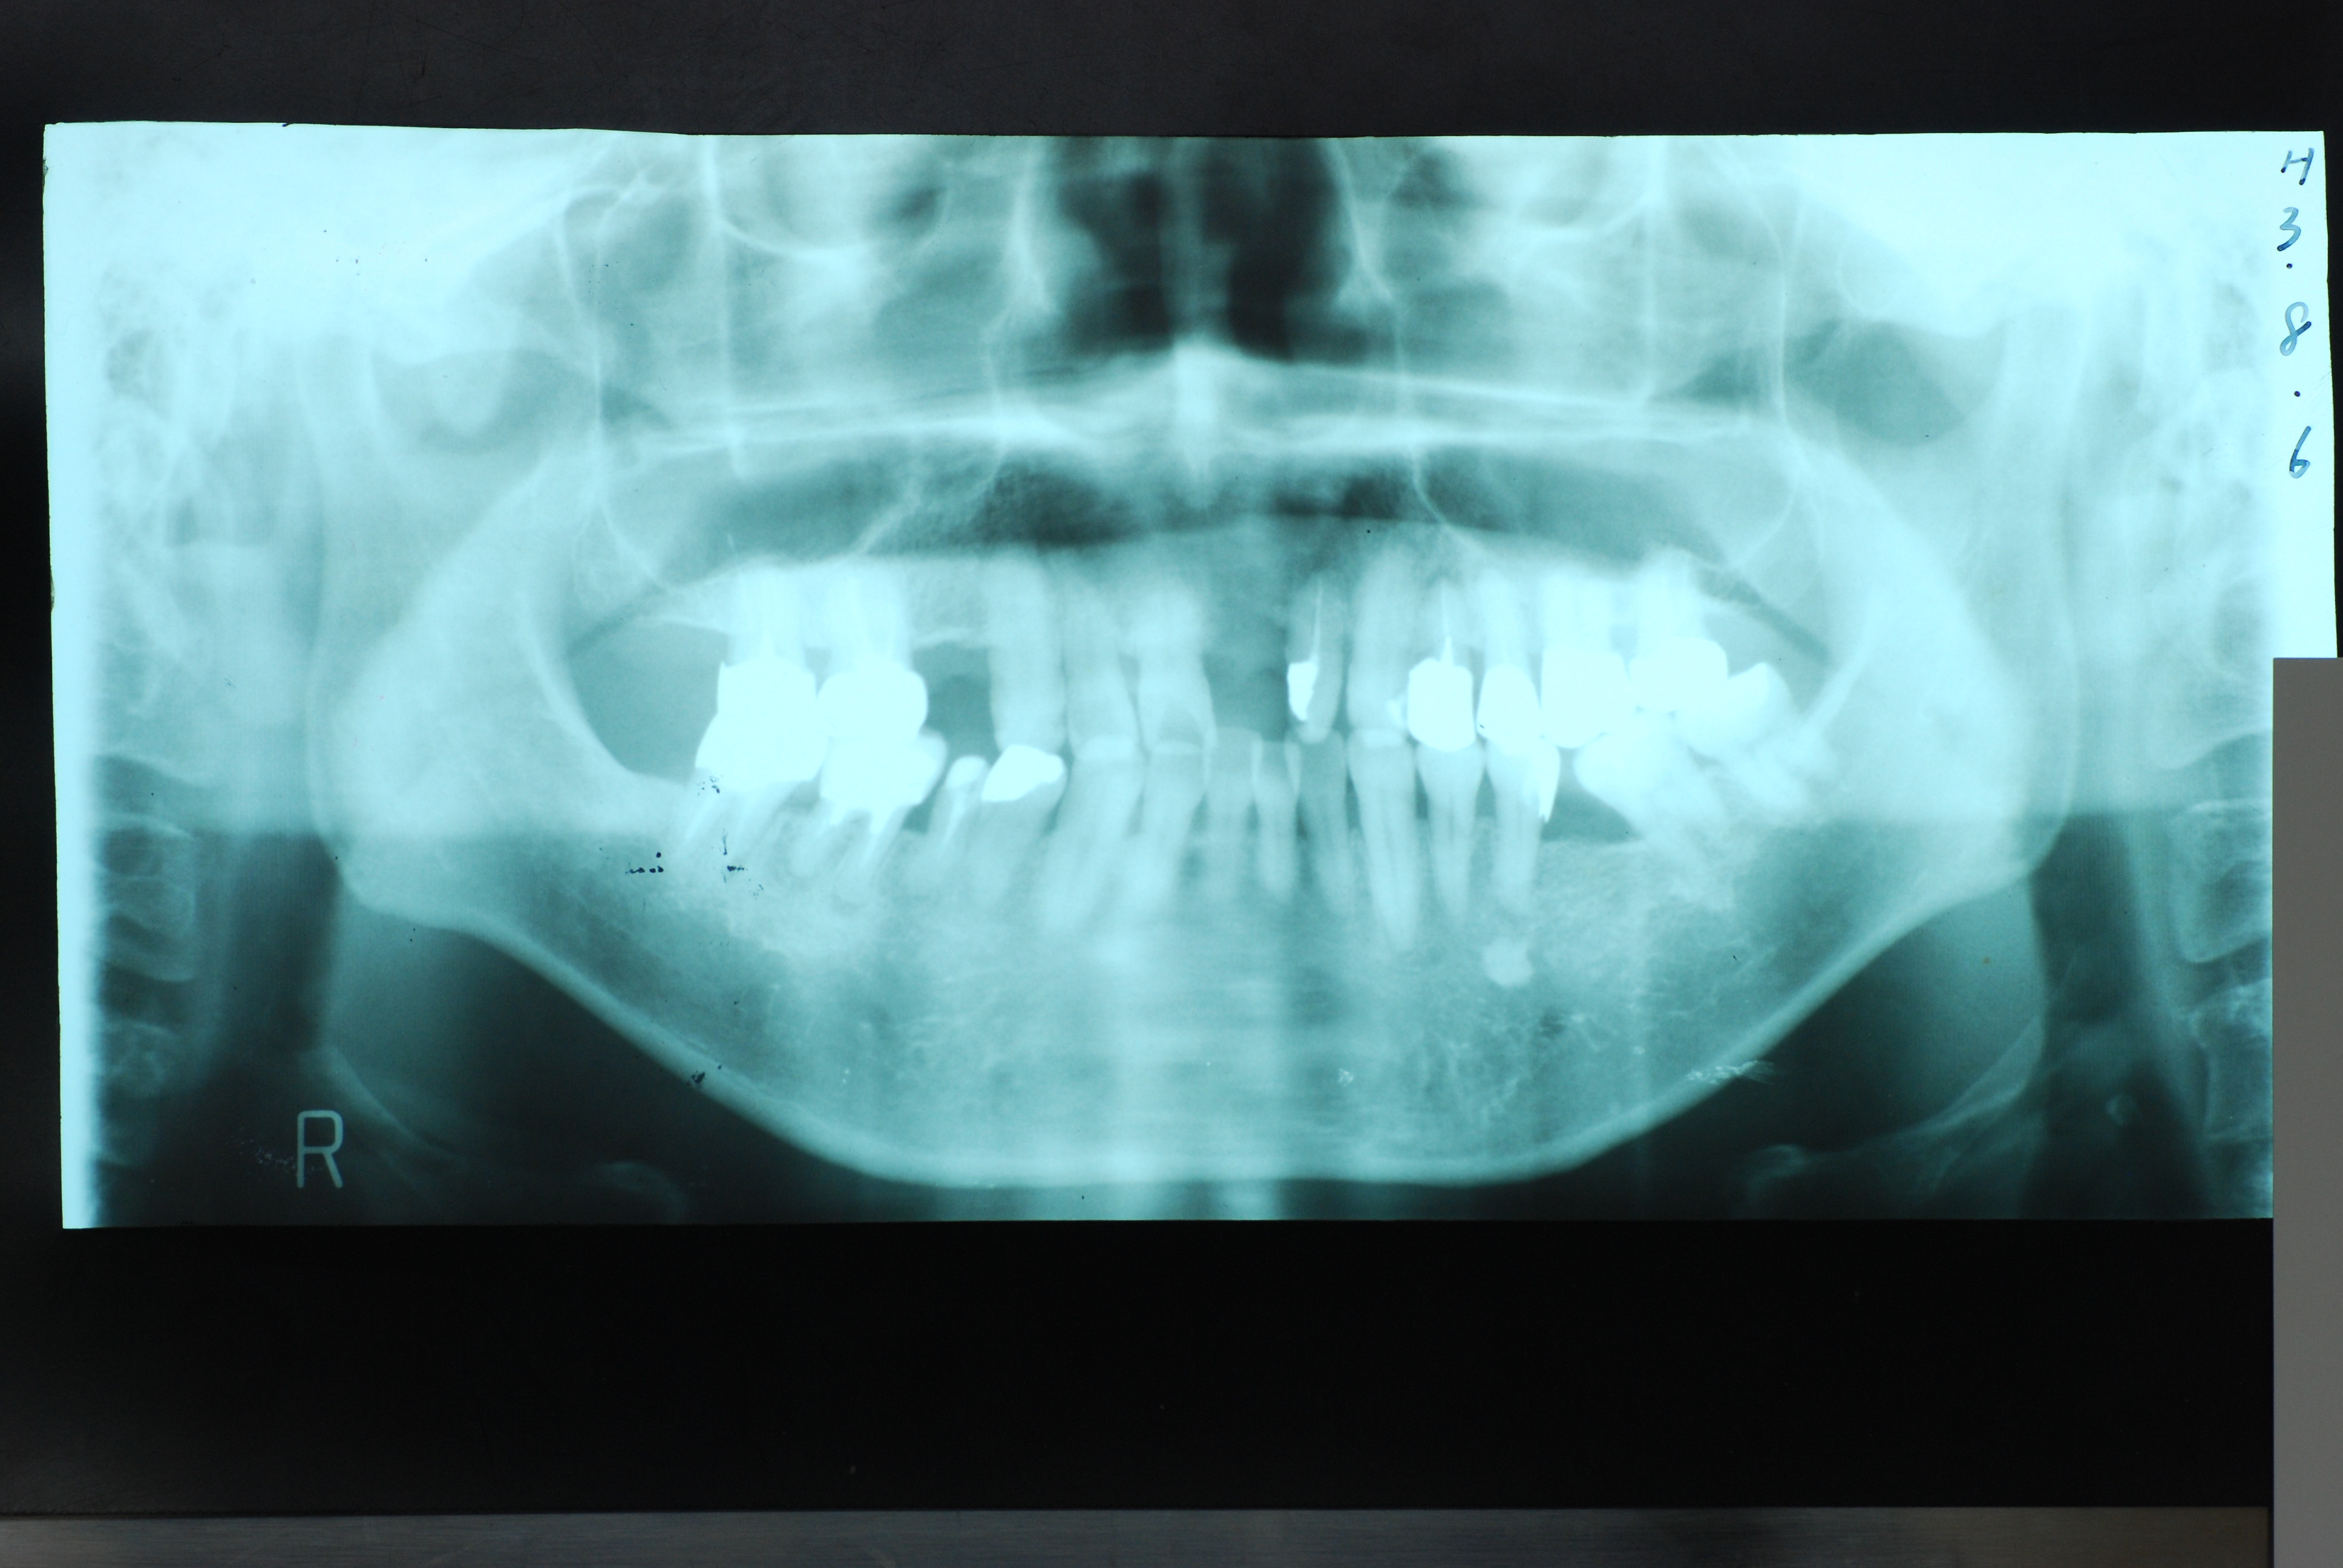

平成3年に治療した患者さんが定期健診にいらっしゃいました。

今のところ一本も悪くなった所はありません。

上顎には本人から見て左に一本、右に二本の歯の喪失があり取り外し式の入れ歯を入れていらっしゃいました。

どうにも発音が悪いという事とレントゲンでは右上の歯が捻転(ねじれている)していて形が悪いという事で来院されました。

当時の写真がないのでX線写真と模型を示します。

DSC_0016DSC_0017

写真右上の歯が曲がっています。 下の写真の上の歯がありません。

平成3年8月5日の日付けが見えます。

DSC_0019DSC_0020

本人では上の左の歯の曲がりを直し、右側は裏側のみ金属にしています。

平成20年のレントゲン写真です。写真の左上と前の方がつながれています。ゴールドクラウンとプラスチックで見える所はカバーしています。

一部前歯がぶつかって欠けたので2年程前に既成品でカバーしました。それで少し先端が変色しているように見えます。

20年以上たってもびくともしないものなのですね。ブラッシングの重要性を強く感じます。当時はお金がないということで超破格のダンピングで